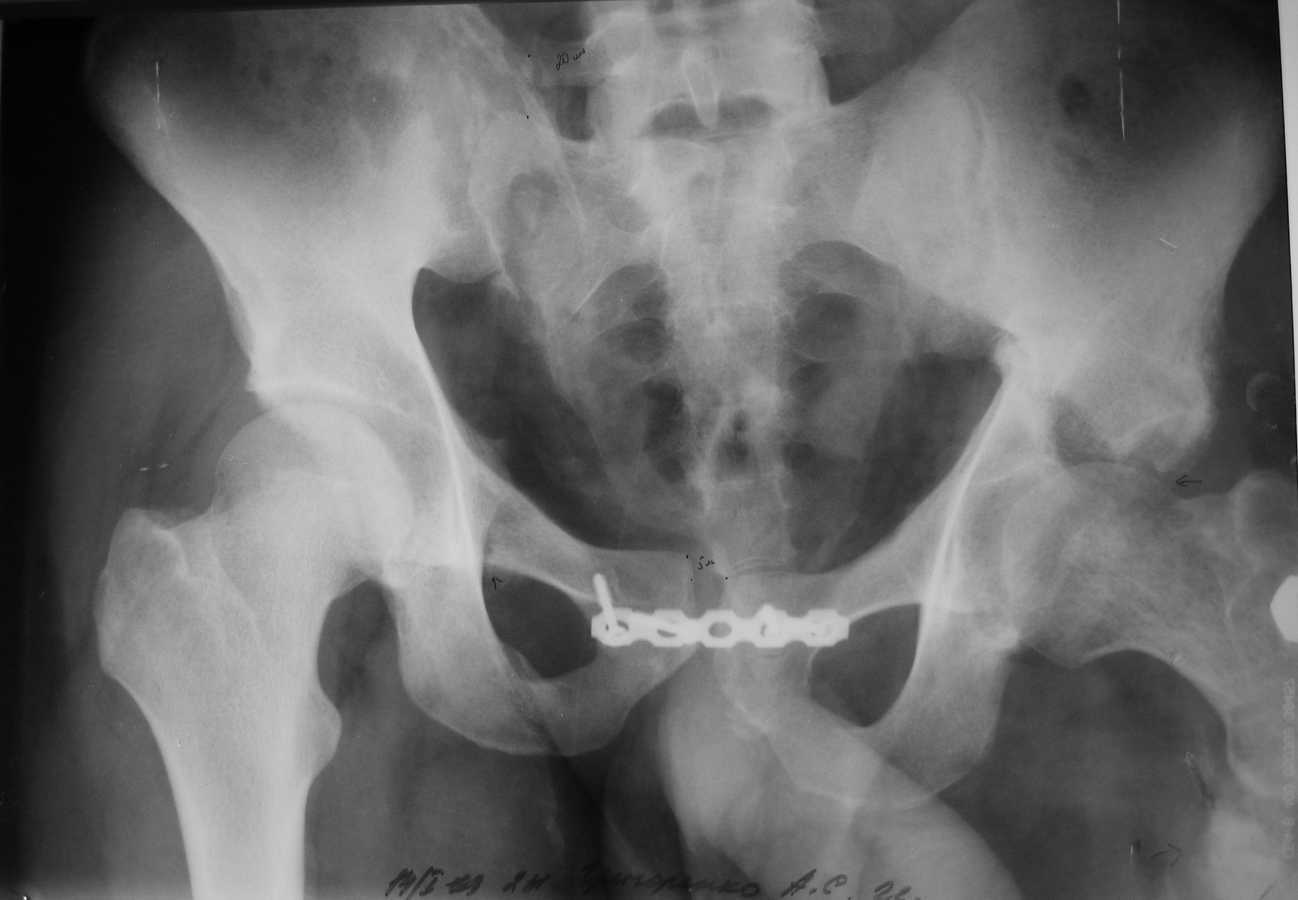

Уважаемые коллеги, у пациента 26 лет имеется дефект в\з бедренной кости образовавшийся в результате СНЭ по поводу травматического остеомиелита

Также имеется травматическая деформация таза с трансвертлужным переломом на стороне дефекта. Планируется замещение дефекта транспортом кости.Хотелось бы услышать ваши советы по поводу оптимальной компоновки АВФ (стержневой, спице-стержневой), есть ли необходимость в дополнительной фиксации за кости таза?

А вот таз - отдельная проблема, вернее, две - краниальное смещение правой половины таза, и нелеченный высокий поперечный перелом вертлужной впадины. Как Вы намереваетесь решать эти проблемы?

Хотел-бы поддержать точку зрения уважаемого А.Н. Челнокова - больших проблем с бедром тут не должно быть, ситуация с тазом куда более серьезная. Судя по крестцово-подвздошному, там более 5 см смещение.

Насчет таза там большие упущения, пластина на симфизе - доказательство отсутствия знания методики лечения переломов таза и ацетабулум. Хотя бы скелетным вытяжением можно было приблизить правую половину таза.

Разрыв крестцово-подвздошного сочленения и поперечный перелом вертлужной впадины являются показанием для оперативного лечения.